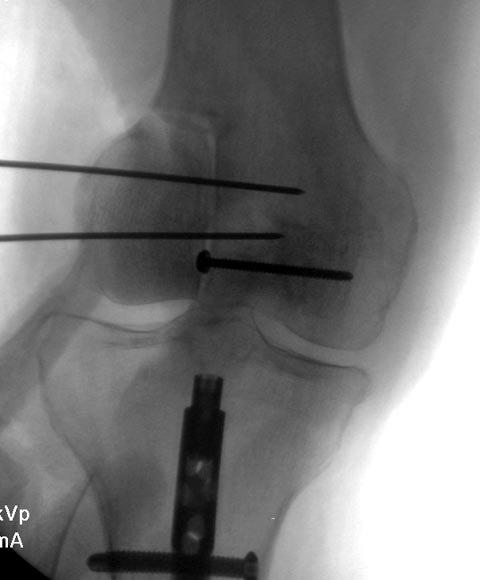

Операция не самая простая. Важно радикально удалить опухоль, при этом сохранить кость, не перфорировать ее в зоне сустава. Этапы операции следующие. Пневмотурникет. Иметь ЭОП.Наружный доступ. Через дефект(можно немного резецировать кости, чтобы было пространство для удаления) по наружной поверхности начать удалять опухоль используя различные костные ложки. Делать это очень аккуратно, беречь кость, постараться не "провалиться" в сустав. Далее тщательная обработка электрокоагулятором всех стенок опухоли. Потом репозиция. Попытаться максимально восстановить анатомию и зафиксировать временно отломки спицами не проходящими через полость опухоли.Рентгенологический контроль. На вышеуказанных этапах возможно целесообразно применение внеочагового дистракционного аппарата внешней фиксации. Сам обходился без этого, но думаю в данном случае сработает лигаментотаксис и поможет в репозиции. Следующий этап заполнение костным цементом, так чтобы не было попадания в сустав. Проконтролировать можно ренгенографически и артроскопически. Это и будет остеосинтез. Удалить металлофиксаторы все. Имею опыт подобных операций не менее 15-20 (перелом был подобный у 1).В остальных случаях было обширное поражение эпиметафиза. Отметил, что при оставление спиц высокий процент рецидива опухоли. Послеоперационная фиксация в шарнирном брейсе. Ранняя функция, нагрузка позняя по ситуации. Конечно? если нет опыта лучше отправить в специализированный центр. С пациентом подробно поговорить, объяснив, что это только попытка сохранить конечность, сустав. Возможна и малигнизация.(во время операции весь материал отправить на исследование). Ранее когда не было цемента и эндопротезов делали артродез с радикальной резекцией очага. Потом стали доступны онкопротезы. Все эти моменты подробно обговорить с больным.

На основании этих данных можно предположить, что здесь имеем ГКТ дистального бедра. Первый случай, оперировать можно в обычном ортопедическом отделении. Доступ латеральный, удалить содержимое и заполнить цементом. Цитотоксичний эффект создается за счет температуры при твердении цемента. И опухоли с вовлечением в процесс более чем 40% нуждаются в дополнительной фиксации, иначе после удаления опухоли может пострадать стабильность. Любая латеральная пластина подойдет для этой цели.

Второй случай, коллапс латерального мыщелка за счет стрессового перелома. До операции надо уточнить диагноз биопсией и определить границу поражения на КТ и МРТ. Здесь имеется вовлечение кортикального слоя и вряд ли дистракционный метод поможет восстановить контур мыщелка. Онкологический вариант замещения с удалением неплохой вариант, но агрессивный. Возраст молодой и при наличии костного банка можно было восстановить аллографтом. Сегодняшняя технология (3Д и КТ) позволяет подобрать идеальный размер целого мыщелка (аллографт).